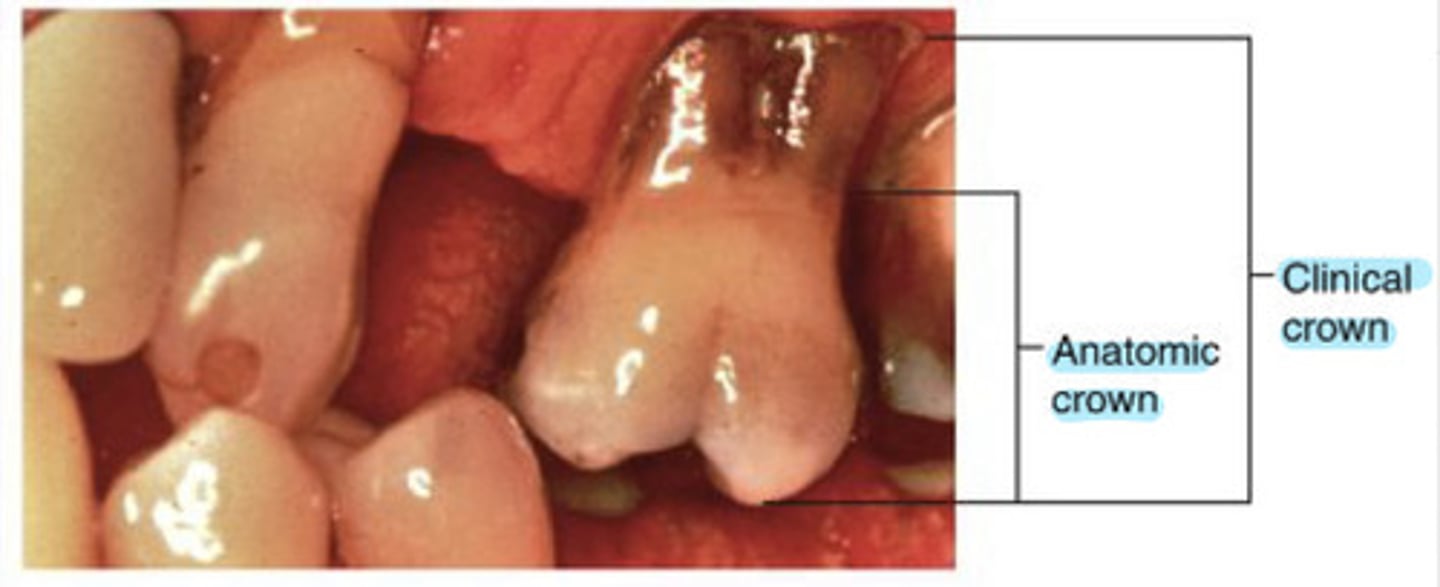

What is the clinical crown?

the amount of tooth that is visible

What is the clinical root?

the portion of the tooth not visible in the oral cavity